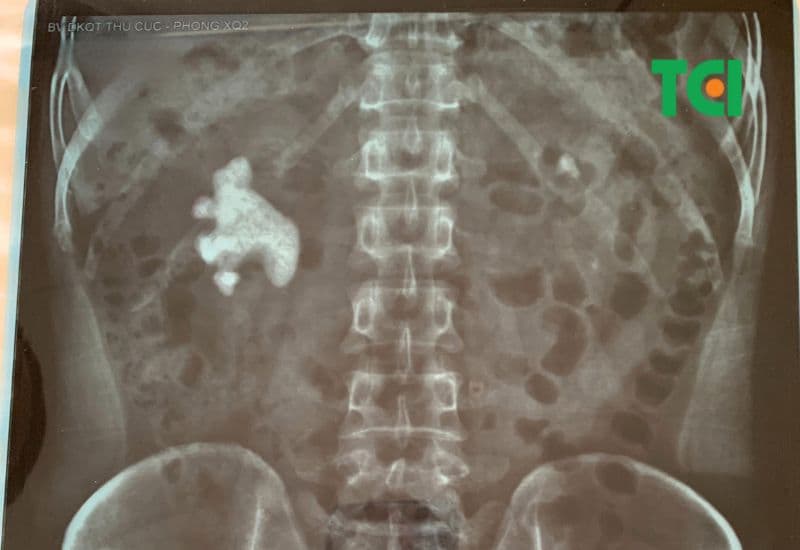

Khác với những loại sỏi thận thông thường có hình tròn hoặc hình bầu dục, sỏi san hô có hình dạng giống như nhánh của san hô, lan tỏa và chiếm toàn bộ hệ thống đài – bể thận. Đây là kết quả của quá trình tích tụ lâu dài các tinh thể khoáng chất và thường liên quan đến nhiễm khuẩn niệu kéo dài. Do có kích thước lớn và cấu trúc phức tạp, sỏi san hô rất khó tán vỡ hoàn toàn bằng những phương pháp điều trị bảo tồn như uống thuốc hoặc tán sỏi ngoài cơ thể. Thậm chí, một số trường hợp còn đòi hỏi phẫu thuật mở – phương pháp vốn tiềm ẩn nhiều rủi ro và thời gian hồi phục kéo dài, mới có thể bóc tách loại bỏ toàn bộ sỏi.

Sỏi san hô là loại sỏi thận phân nhánh bám chặt và phủ kín các đài bể thận của người bệnh, khiến nguy cơ chức năng thận bị suy yếu nhanh